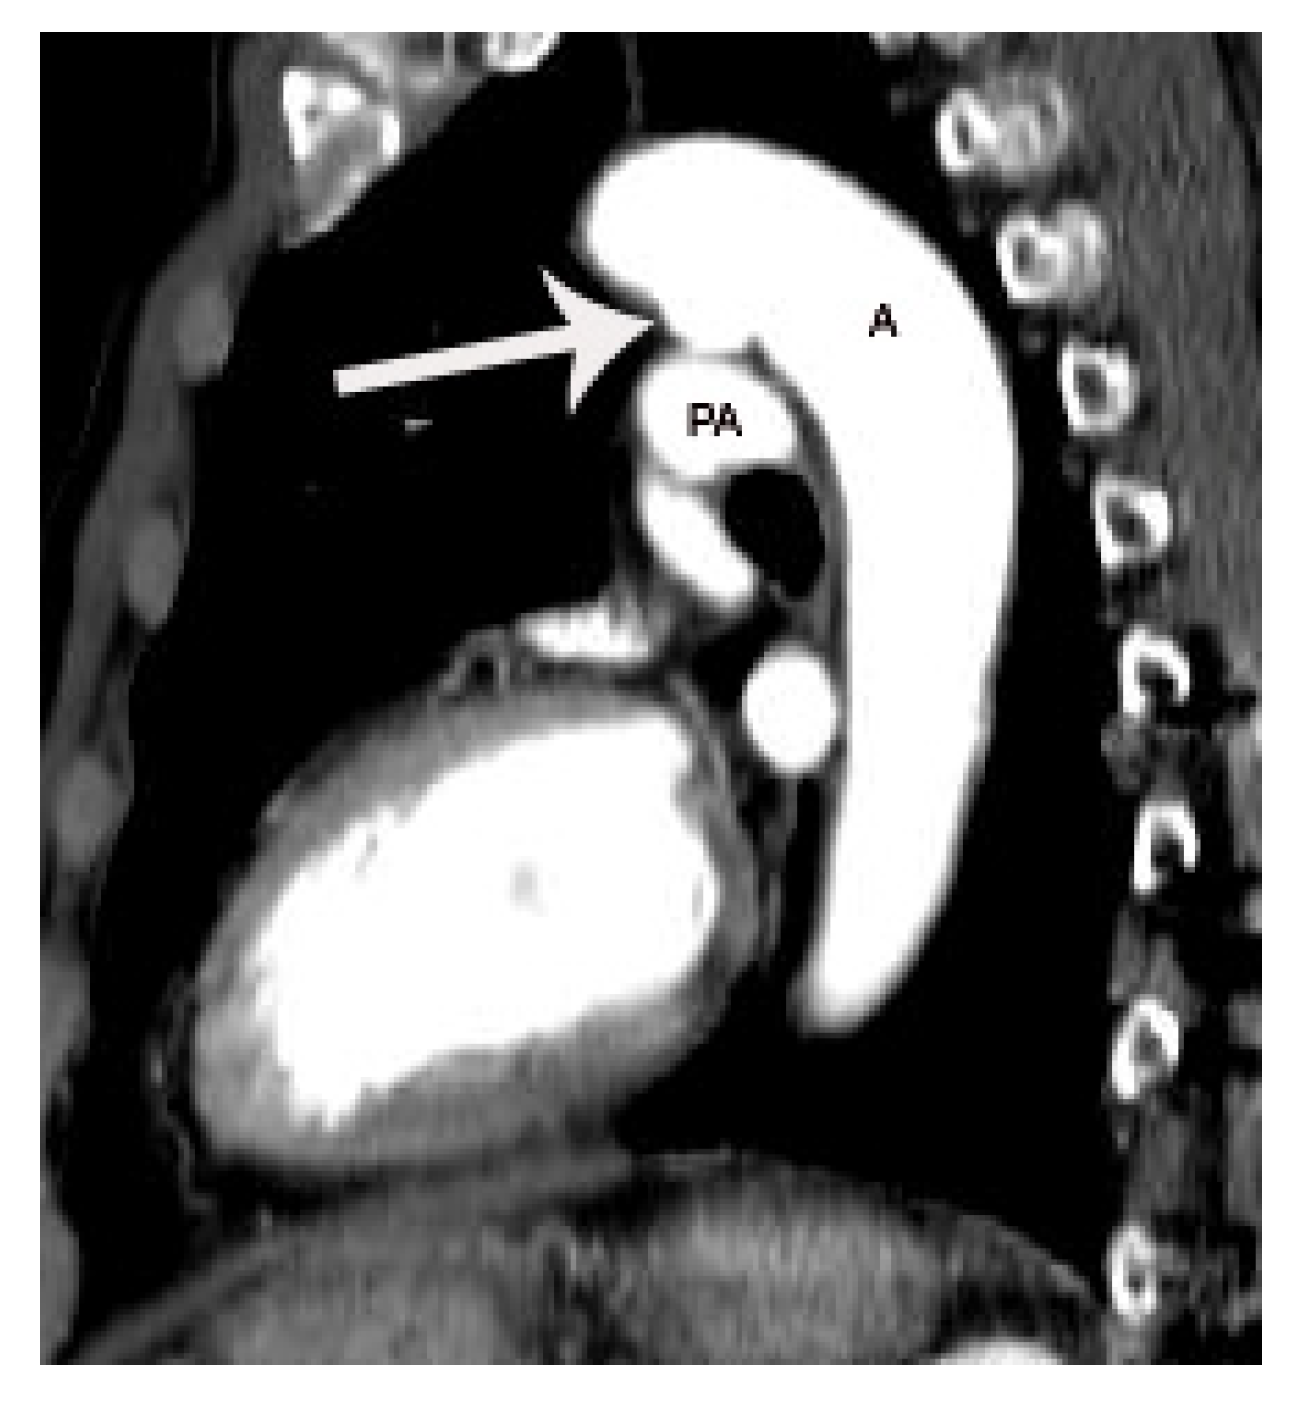

5. CT Anatomy of PDA

6.1. Potential Role of CT in Moderate-to Large-Sized PDA

8.2.2. Potential Use of CT Prior to Transcatheter Closure of PDA